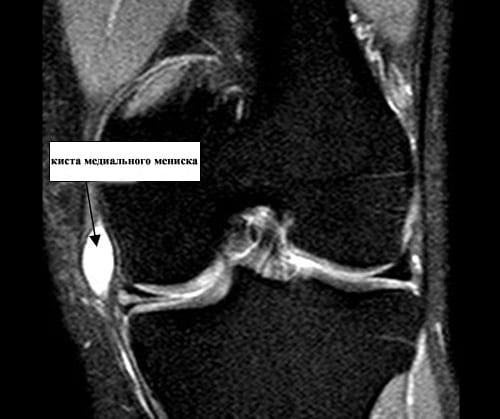

- киста мениска. В колене у каждого человека имеются хрящевые прокладки, которые служат «амортизатором», в анатомии их называют менисками. Иногда в них появляется жидкость, которая отрицательно влияет на работу сустава. Обнаруживает себя патология сильной, неожиданной болью в колене, сконцентрированной во внутренней части колена. Симптомы бывают разные, но, как правило, этому типу опухоли предшествует слабость в мышцах бедра. Народными средствами в таком случае не обойтись, так как здесь требуется операционное вмешательство, а именно лечение под названием артроскопия;